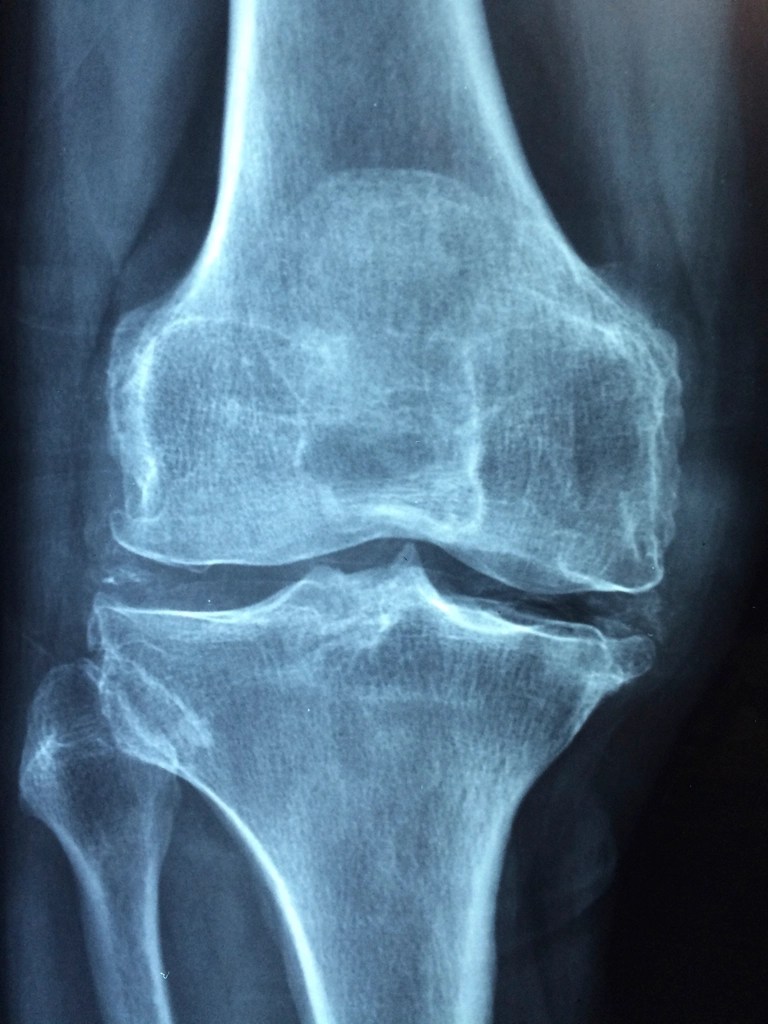

Total Hip and Knee Replacement Rehabilitation : What to expect.

Embarking on a major surgery, such as Total Hip or Knee Replacement, can be daunting.

Knee – Ligament strains – Patella Tendonitis – Osgood Schlatter disease – Patellofemeral pain syndrome – Popliteus pain – Patellar Tracking issues – Meniscal tears .